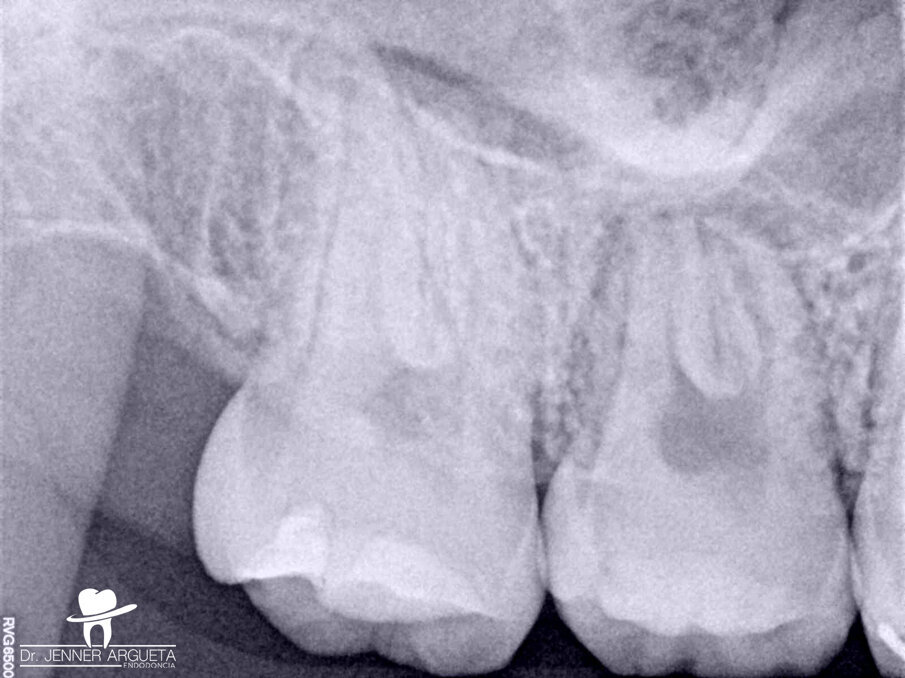

A 16-year-old female patient was referred to the office for evaluation of tooth #16 (Fig. 1). The referring dentist asked that we apply all the available resources to save the tooth. The diagnosis was previously treated and symptomatic periapical periodontitis. After detailed examination, it was concluded that the tooth was not restorable. With the parents’ and patient’s agreement, we decided on an autogenous transplantation of tooth #18 to the site of tooth #16 after its extraction (Fig. 2). The orthodontist had determined that tooth #18 was to be extracted, and it was intended that the patient’s occlusion should be balanced by the end of the orthodontic treatment. Teeth #16 and 18 were extracted in the least traumatic way possible. After minor bone remodelling of the socket using low-speed burs, the third molar was transplanted to the recipient site (Fig. 3). A nylon monofilament flexible splint was used to keep the tooth in place (Fig. 4). Fifteen days later, the splint was removed, healthy soft tissue was observed, the patient was asymptomatic, and the tooth was stable in the site (Figs. 5a & b).

Fig. 2: Periapical radiograph of the maxillary right molar. Tooth #18 was to be transplanted to the site occupied by tooth #16.